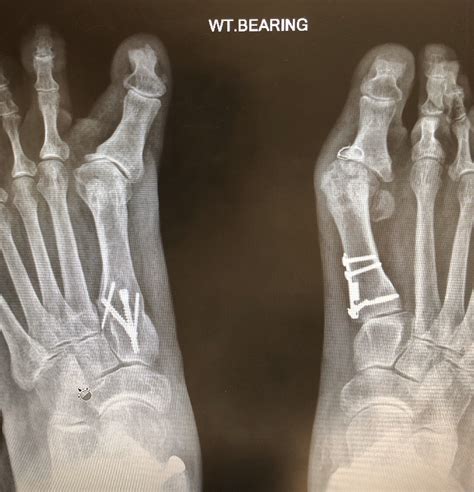

A successful bunionectomy involves precise bone cuts (osteotomies) and fixation to realign the joint. When the surgery fails, it usually falls into one of these distinct categories, each with its own visual signature that is often documented in failed bunion surgery pictures.

The surgical correction involves cutting and repositioning the metatarsal bone. Nonunion means the bone fragments fail to fuse together (heal) at all, which is extremely painful and causes instability. Malunion means the bones heal, but in a poor or incorrect position. Radiographs (X-rays) are critical in diagnosing these failures, but the physical signs include chronic pain, swelling, and a visible step-off or abnormal contour at the surgical site. This is a common technical complication that revision surgeons at specialized centers often have to fix.

Bunionectomies typically use screws, plates, or wires to hold the bone fragments in their new position. Failure can occur if the hardware breaks, loosens, or migrates, causing irritation to soft tissues or the skin. In failed bunion surgery pictures, the hardware may be visibly prominent or palpable under the skin, requiring removal. While hardware removal is a common secondary procedure, it is considered a failure if the hardware itself is the source of the chronic pain or if its failure leads to malunion.